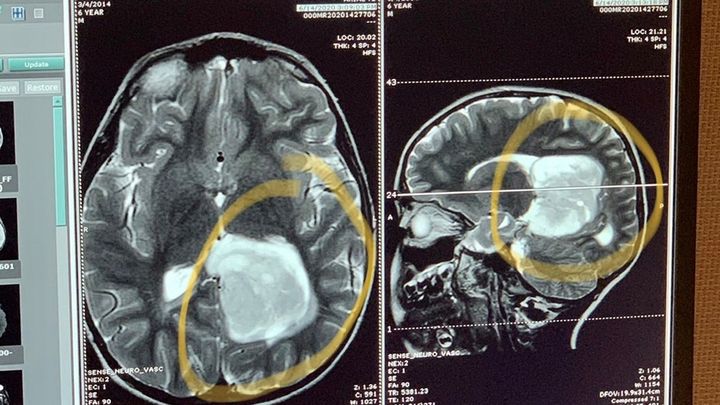

We (Tim and Renee-Grandma and Grandpa) found out on Saturday 6/13 our Grandson Brody who is 6 years old, was having seizures and was rushed to the Emergency room. A Cat scan revealed an egg sized mass in his brain. He was transferred to Children’s Hospital LA where they performed an MRI to discern its Actual location. Brody underwent 6 hours of Brain surgery and it seems to have been a successful one!!! Now the recovery begins and the hopes are “High” there will be no deficits as Brain surgery is a delicate process. All this is going on while his parents are closing on a home sale this Friday 6/19. They scraped together all they had for a down payment and closing costs. Brody’s family is doing everything they can to support during this stressful time. We are asking for any support to help This young family with Brody’s medical bills that are mounting up!!! We appreciate all the prayers and support thus far!!!

We (Tim and Renee-Grandma and Grandpa) found out on Saturday 6/13 our Grandson Brody who is 6 years old, was having seizures and was rushed to the Emergency room. A Cat scan revealed an egg sized mass in his brain. He was transferred to Children’s Hospital LA where they performed an MRI to discern its Actual location. Brody underwent 6 hours of Brain surgery and it seems to have been a successful one!!! Now the recovery begins and the hopes are “High” there will be no deficits as Brain surgery is a delicate process. All this is going on while his parents are closing on a home sale this Friday 6/19. They scraped together all they had for a down payment and closing costs. Brody’s family is doing everything they can to support during this stressful time. We are asking for any support to help This young family with Brody’s medical bills that are mounting up!!! We appreciate all the prayers and support thus far!!!

We (Tim and Renee-Grandma and Grandpa) found out on Saturday 6/13 our Grandson Brody who is 6 years old, was having seizures and was rushed to the Emergency room. A Cat scan revealed an egg sized mass in his brain. He was transferred to Children’s Hospital LA where they performed an MRI to discern its Actual location. Brody underwent 6 hours of Brain surgery and it seems to have been a successful one!!! Now the recovery begins and the hopes are “High” there will be no deficits as Brain surgery is a delicate process. All this is going on while his parents are closing on a home sale this Friday 6/19. They scraped together all they had for a down payment and closing costs. Brody’s family is doing everything they can to support during this stressful time. We are asking for any support to help This young family with Brody’s medical bills that are mounting up!!! We appreciate all the prayers and support thus far!!!